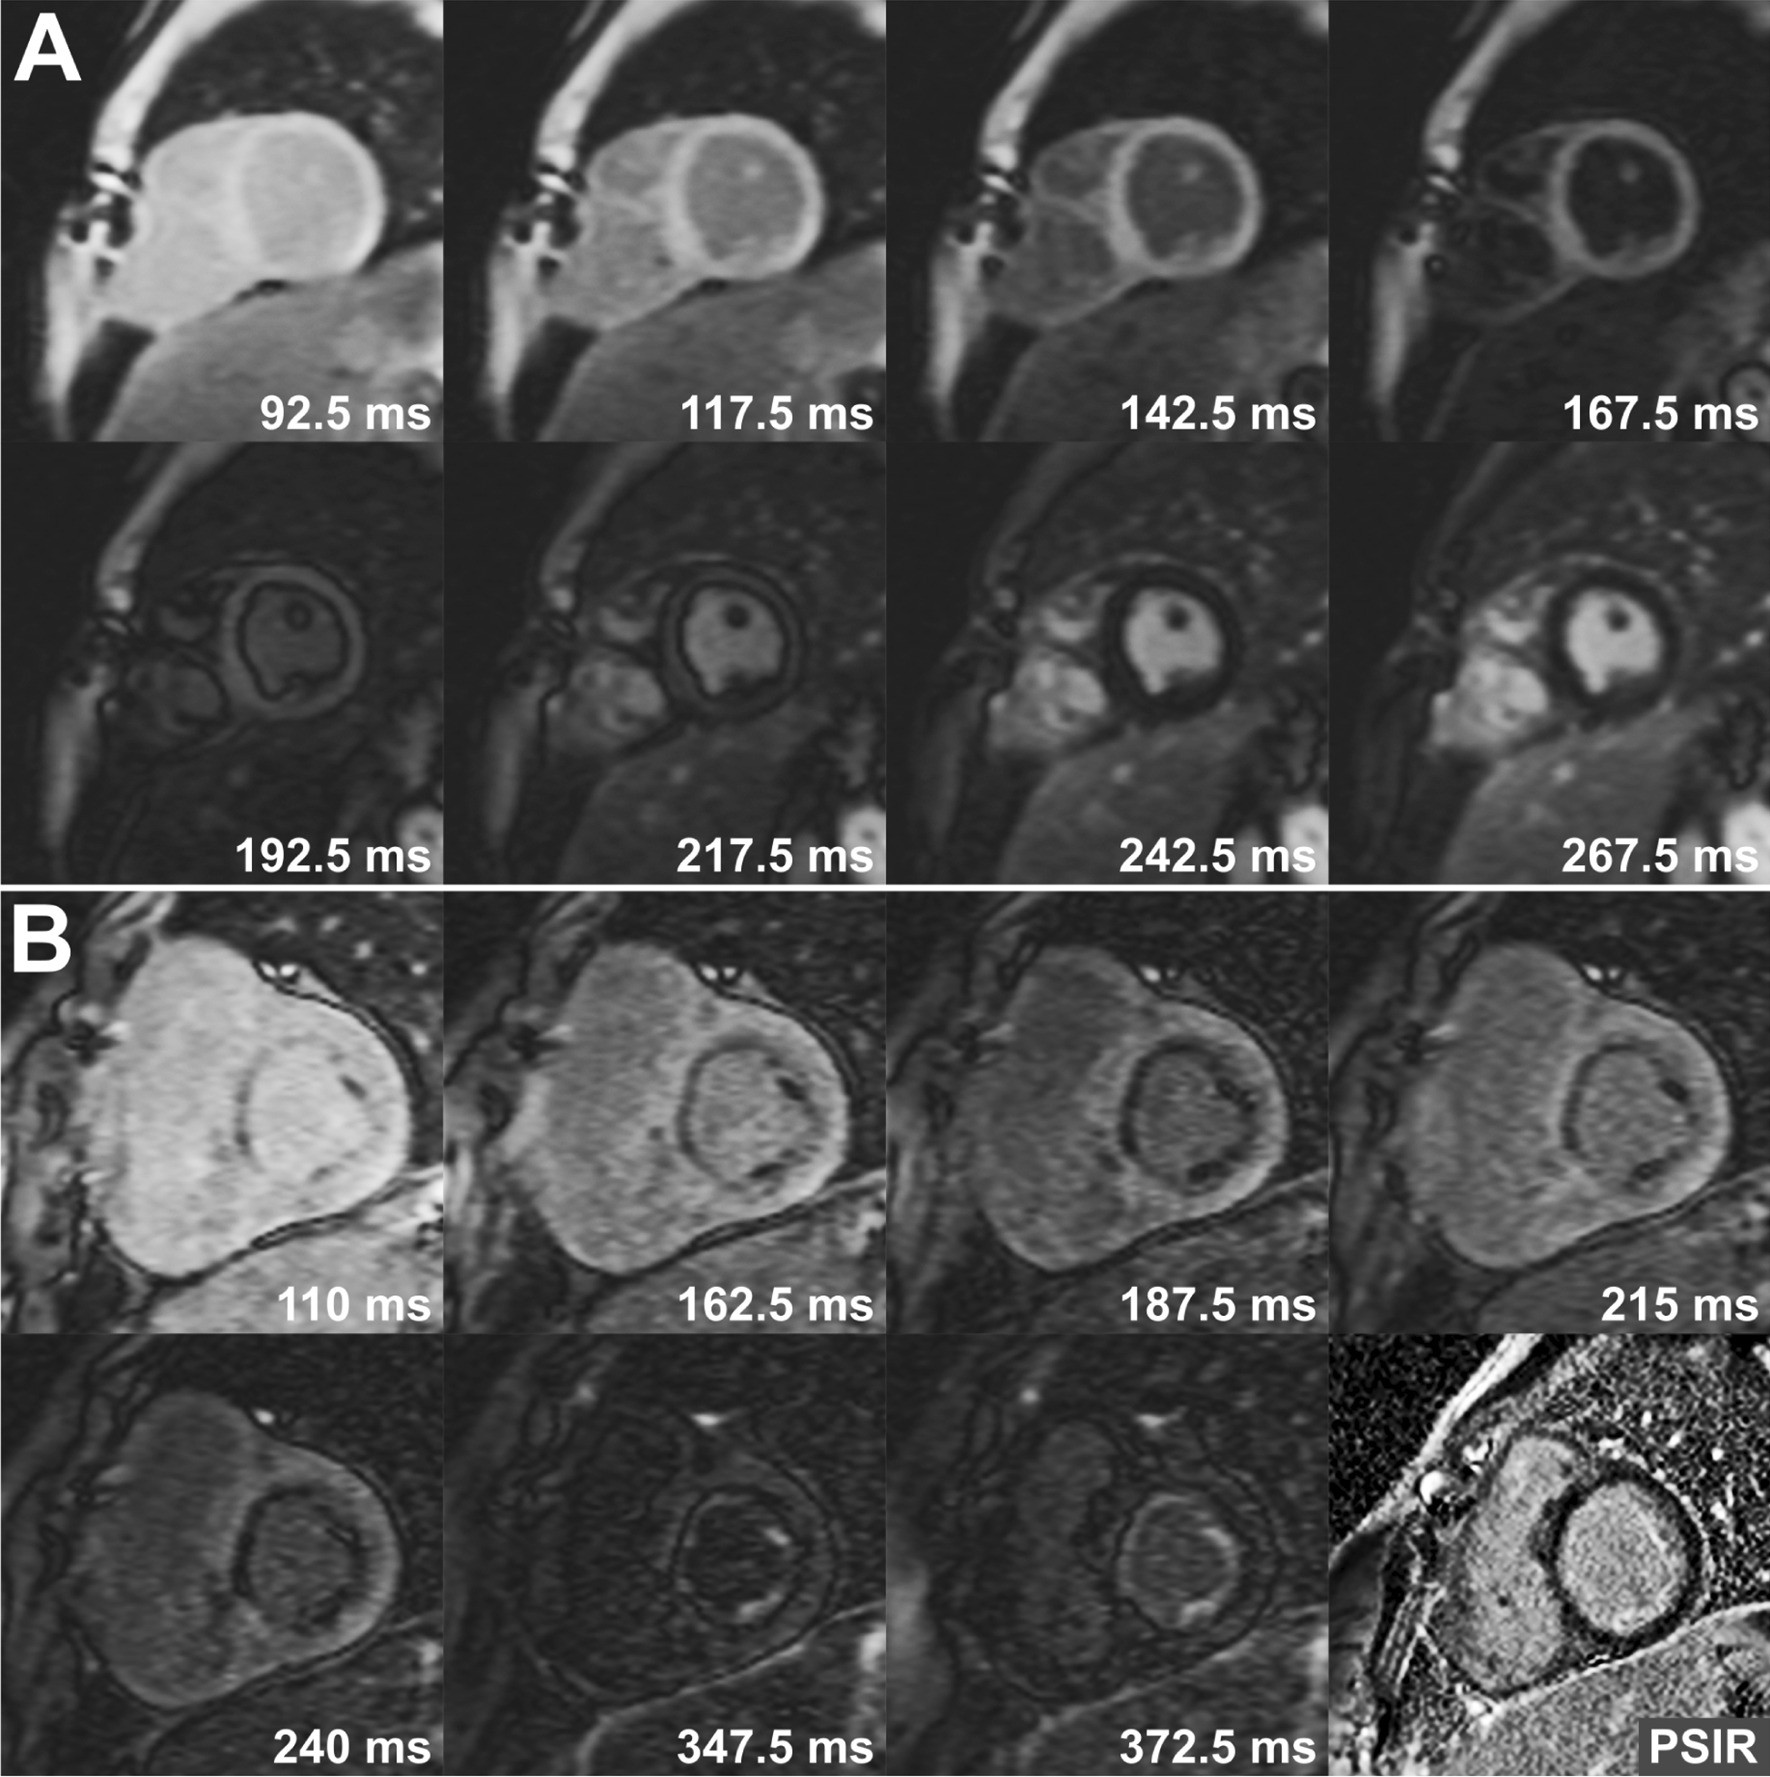

Fig. 1

From: Usefulness of TI-scout images in the assessment of late gadolinium enhancement in children

TI-scout images showing different signal intensity recovery after inversion pulse in normal (a) and abnormal (b) myocardium. In images obtained from a patient with aortic stenosis (b), there is obvious endocardial/subendocardial fibrosis in all TI-scout images with changing signal intensity. Note that late gadolinium enhancement (LGE) is barely identifiable in phase sensitive inversion recovery (PSIR) image in right lower corner